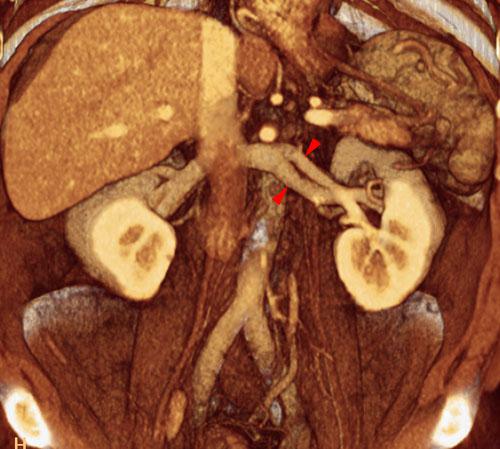

Bifurcación vena renal izquierda

VR seccional. Visión coronal anterior. AngioTC renal en fase venosa visualizándose una bifurcación prehiliar de la vena renal izquierda (puntas de flecha)